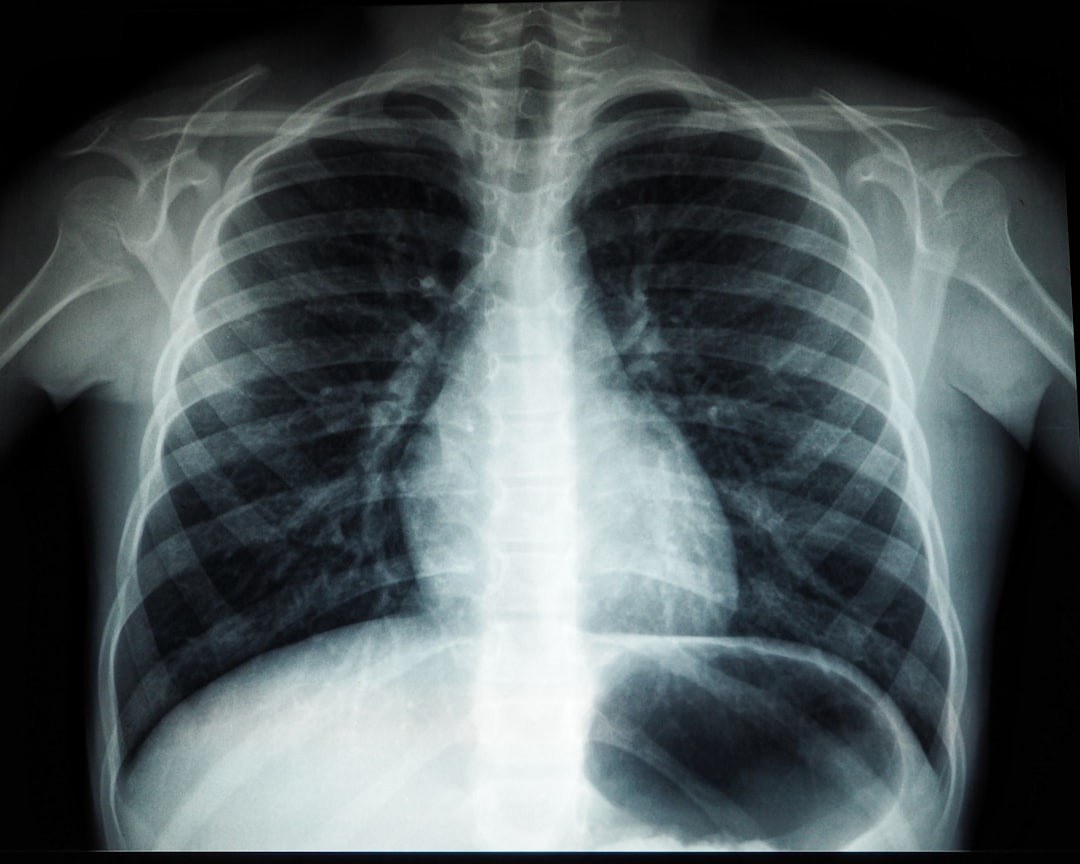

잠복결핵 검사란 결핵균에 노출되었지만 현재 결핵 증세가 없는 상태에서 실시하는 검사입니다. 이 검사는 누가 결핵균에 노출되었는지를 판단하는 데 도움을 줄 수 있습니다. 검사 결과가 양성일 경우, 치료가 필요할 수 있습니다. 검사 방법으로는 피부 검사와 혈액 검사 두 가지가 있습니다. 각 방법은 특성에 따라 다르게 진행되며, 상황에 맞게 선택될 수 있습니다. 이러한 과정을 통해 잠복결핵 검사에 대한 더 많은 이해로 나아가실 수 있을 것입니다.

잠복결핵 검사란?